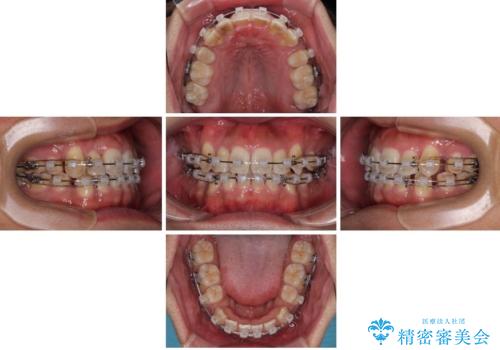

- 矯正装置

- クリアブラケット

- 治療期間

- 2年3ヶ月

- 治療回数

- 30回以上

矯正装置は、審美性と費用面のバランスを考慮して、プラスチックブラケットとメタルワイヤーを使用しました。

透明感のあるブラケットを用いたため、従来の金属装置よりも目立ちにくく、日常生活での見た目の不安も軽減できます。

八重歯はきれいに整い、前歯もバランスよく収まり、横顔のラインも自然に改善されました。

治療後、患者様は「思い切り笑えるようになった」と大変喜んでくださいました。